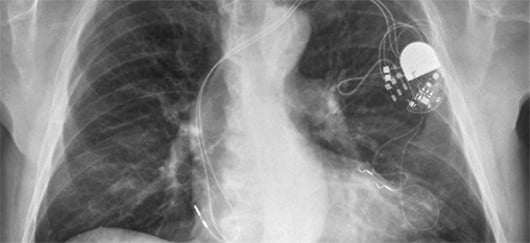

Un stimulateur cardiaque bientôt relié à une biopile? (©photo)

Un pacemaker auto-rechargeable

Cette application pourrait permettre aux personnes équipées de stimulateurs cardiaques d’éviter les interventions dues à l’épuisement de leurs batteries : la batterie d’un pacemaker doit par exemple être généralement changée tous les 10 ans. La biopile pourrait en outre être positionnée plus près du cœur et être employée dans davantage d’insuffisances cardiaques qu'avec les piles employées jusqu'ici. Les chercheurs travaillent dans ce sens avec la société italienne Sorin, spécialisée dans ce domaine. De nombreuses autres applications sont envisageables, cette biopile pouvant alimenter tout appareil implanté dans le corps d'un humain ou d'un animal.